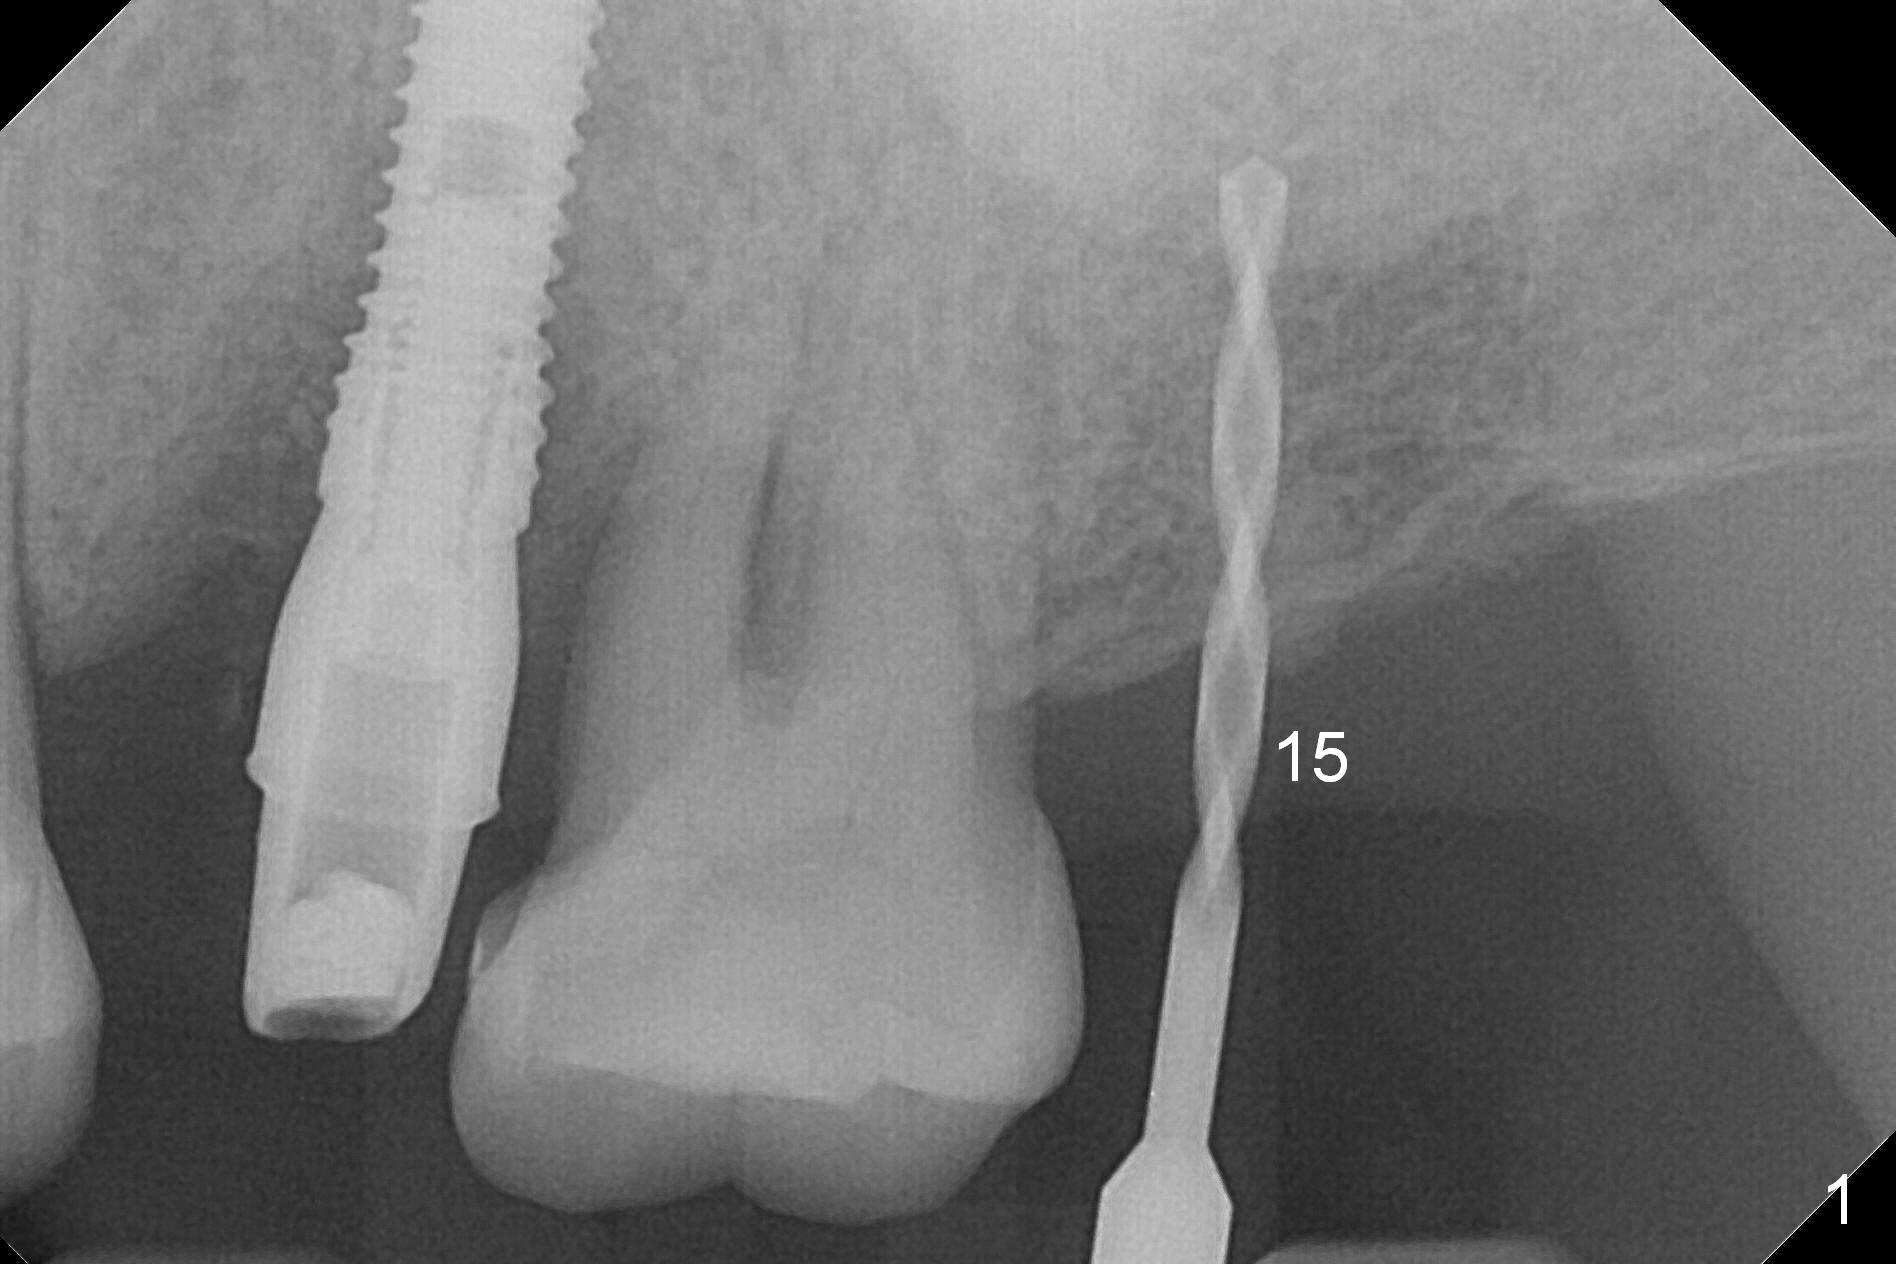

A 1.2 mm initial drill is used to start osteotomy at the site of #15 (Fig.1). After moving the osteotomy distally (with Lindamann bur), the osteotomy is enlarged by DIO Bone Expanders until 2.4/3.7 mm for 18 mm (gingival level) (Fig.2). Following the expander 3.0/4.4 mm, a 5x13 mm UF implant is placed supracrestal (Fig.3,4). After deepening the osteotomy with 3.8 mm drill for 3 mm, the implant is placed deeper by ~ 2 mm (Fig.5 arrow). Since the tooth #18 is supraerupted, a healing abutment (5.5x12(3) mm) is placed (Fig.6: H); the gingiva adapts to the abutment well. Suture is not necessary. The bone remains stable 2 and 4.5 months postop (Fig.7,8). Impression is taken. A crown is delivered nearly 6 months postop (08/07/2017). While there is minimal bone loss at #13 and 15 three years and 4 months post cementation, the tooth #14 and 18 are mobile (Fig.13,14, #13).